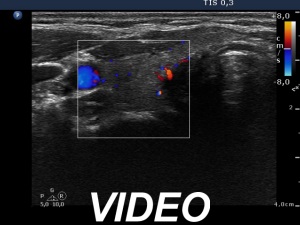

Examination 5 months later (3rd row of images):

Laboratory tests: minimal degree of hypothyroidism (TSH 4.08 mIU/L, FT4 11.5 pM/L), CRP 0.7 mg/L.

Ultrasonography: the thyroid decreased in size as did the extent of hypoechogenic areas. The vascularization was unchanged. There was a cystic lesion presenting microcalcification in the solid part in the lower part of the right lobe. We reviewed the video of the first examination and noticed that the lesion was already present but much smaller. The difference in size was explained by the lack at cystic component at first investigation.

Cytology from the cystic lesion in the right lobe resulted in papillary carcinoma.